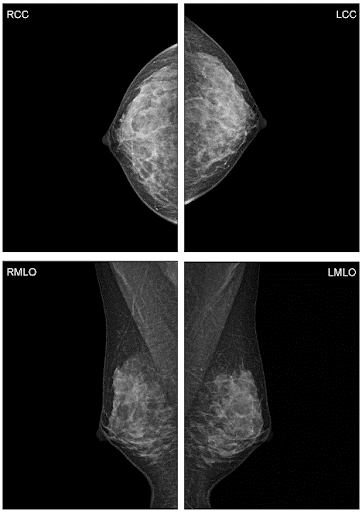

Шаг 1. Аналоговая или цифровая маммография

Шаг 2. Виды цифровой маммографии

Шаг 8. Нужна ли функция цифрового томосинтеза (DBT)?